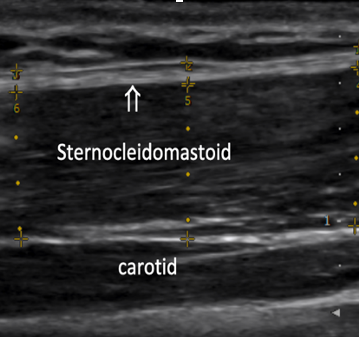

A key component of this evaluation is the use of ultrasound elastography, a specialized imaging technique that measures both the thickness and stiffness of deep fascia. In hypermobile spectrum disorders, excess extracellular matrix deposition leads to an increase in deep fascia thickness, while the stiffness of the fascia, as assessed by elastography, is often lower than normal. This reduction in stiffness reflects underlying connective tissue changes that contribute to the clinical manifestations of hEDS. The integration of these advanced diagnostic tools aids in a more accurate diagnosis and provides insights into the structural abnormalities of the fascia and tendons, facilitating targeted therapeutic strategies.

SCM Fascia Thickness (normal < 1.5mm) SCM Strain index (normal SI approximately 2.1)